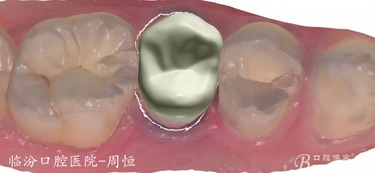

嵌體位于牙體內(nèi)部,只能修復(fù)缺損的牙體組織,不能保護(hù)剩余的牙體組織。

嵌體在咬合受力后會(huì)將力傳導(dǎo)至洞的側(cè)壁,在剩余牙體內(nèi)產(chǎn)生拉應(yīng)力,過大的拉引力會(huì)造成牙體折裂。 要避免咬硬物,注意勿進(jìn)食過硬食物,以免因給牙齒帶來過大的負(fù)荷而影響嵌體的長(zhǎng)期使用。

嵌體位于牙體內(nèi)部,只能修復(fù)缺損的牙體組織,不能保護(hù)剩余的牙體組織。嵌體在咬合受力后會(huì)將力傳導(dǎo)至洞的側(cè)壁,在剩余牙體內(nèi)產(chǎn)生拉應(yīng)力,過大的拉引力會(huì)造成牙體折裂。